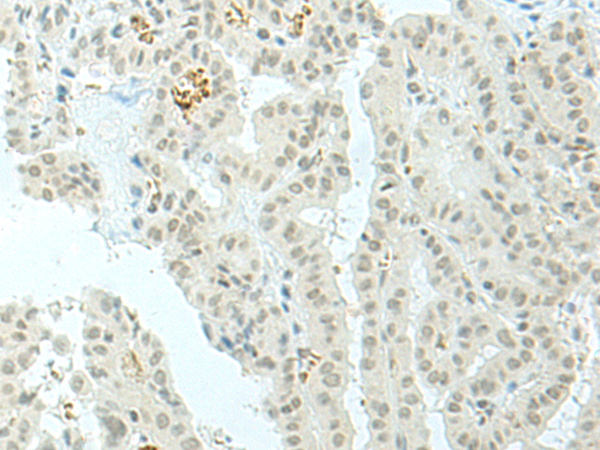

IHC positive control: |

Human lung cancer and Human thyroid cancer |

IHC Recommend dilution: |

30-150 |